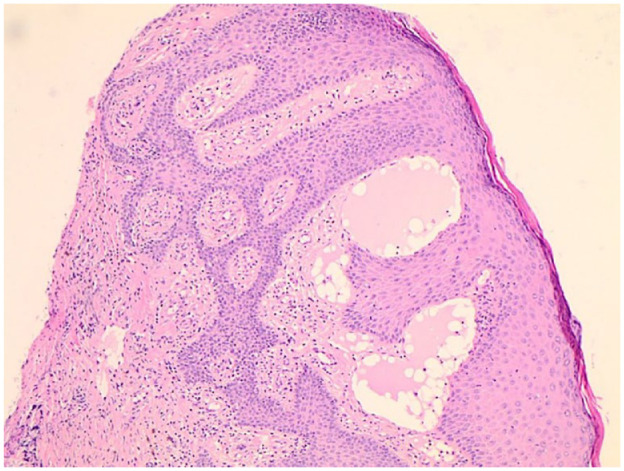

Idiopathic granulomatous vulvitis is an uncommon anogenital area disease described in the last few decades. It causes an inflammatory reaction that culminates in swelling and possibly distortion of the female anogenital area. Many reported cases consider this non-infectious entity the genital counterpart to granulomatous cheilitis. We here present a 64 years old female patient with idiopathic granulomatous vulvitis co-existing with lipodermatosclerosis, with the excellent response of the former condition to hydroxychloroquine and potent topical steroids.

Abstract Image